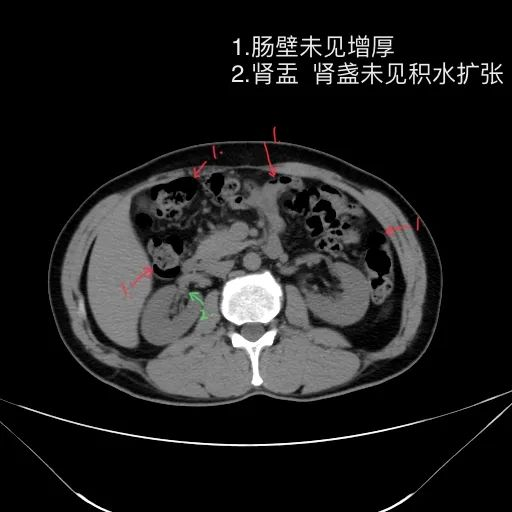

肝脏缩小,包膜凹凸不平,肝裂增宽,各叶比例失衡,肝实质密度不均,肝S4小片低密度影,约cm;胆囊不大,其内未见异常密度影,胆道系统未见扩张;胰腺、脾脏形态、密度、大小未见异常;双肾上腺及双肾形态、密度、大小未见异常,双输尿管未见扩张,膀胱充盈良好,壁光滑,其内未见异常密度影;前列腺未见异常;胃肠道未见充盈,壁未见明确增厚,食管胃底多发迂曲、增粗血管,腹部及腹膜后未见肿大淋巴结;腹水。

5.双肾位置,大小,密度,周围,集合系统,然后连续看双输尿管及膀胱